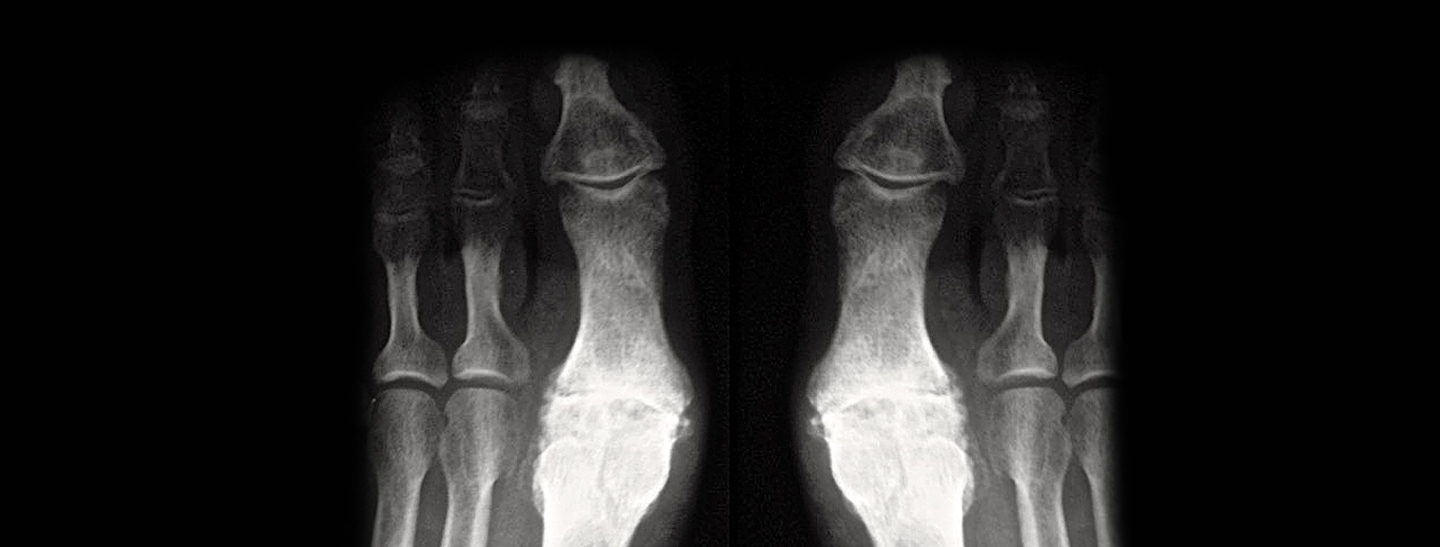

Il Dr. Stefano Fieschi è impegnato da diversi anni nella chirurgica del piede e caviglia, con particolare riferimento ad alcune patologie come per esempio la sostituzione articolare con spaziatore SilkToe per l’alluce rigido.

In virtù degli ottimi risultati sin ora ottenuti a oltre 20 anni dal primo impianto il Dr. Stefano Fieschi è consulente e referente in Europa dell’azienda produttrice dello spaziatore (divulgazione, insegnamento ecc)